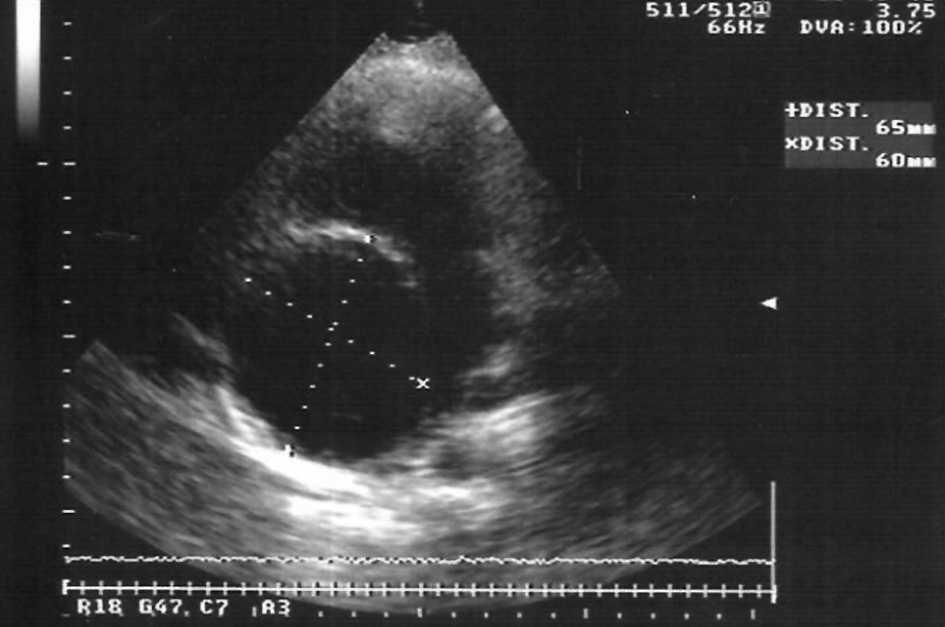

Los controles ecocardiográficos maternos (fig. 1) fueron similares a los preconcepcionales, hasta que en semana 33+6 se evidenció un leve aumento subjetivo de la insuficiencia aórtica (ligera-moderada) y un incremento del tamaño de la aurícula derecha (diámetro máximo de 67 mm).

Figura 1. Medición ecográfica de los diámetros máximos de la aurícula derecha cardíaca materna.